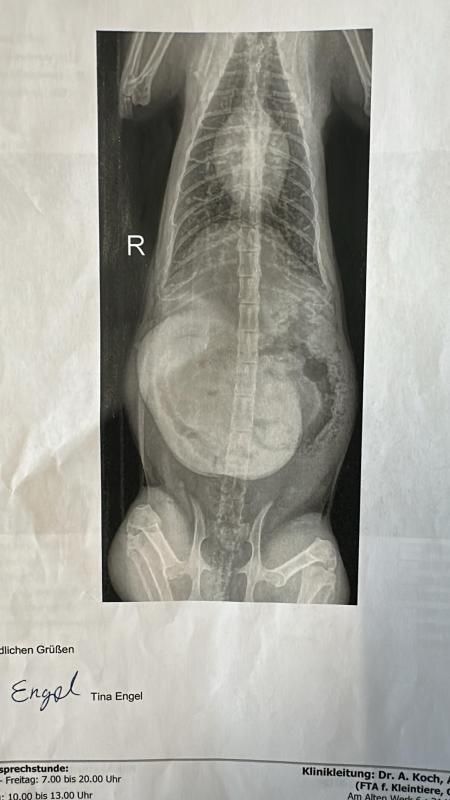

Hedwig kam am 16.09.25 zusammen mit ihren ca. 1 Tag alten Kitten zu uns ins Tierheim. Leider verstarben drei der insgesamt 4 Kitten in kürzester Zeit…Hedwig war aus gesundheitlichen Gründen nicht in der Lage, ihre Babys zu versorgen. Sie muss schon vor längerer Zeit einen Bauchdeckenbruch erlitten haben, in dem bereits Darmschlingen zu sehen waren. Hedwig wurde schnellstmöglich operiert, um sie endlich von den Schmerzen und Leiden zu befreien ! Nun muss sich das freundliche Mädchen erst wieder richtig erholen und ist dann auf der Suche nach einer tollen Familie, welche ihr ganz viel Liebe und Geborgenheit nach dieser furchbar schweren Zeit schenken möchte. Das letzte verbliebene Kitten „Zuma“ lebt übrigens bei einer Pflegestelle und wird mit dem Fläschchen aufgezogen…die kleine Motte entwickelt sich ganz toll !